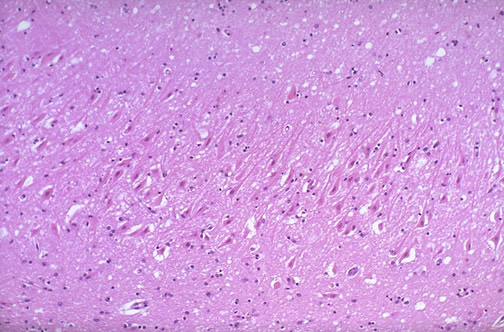

The neurons are the most sensitive cells to anoxic injury. Seen here are red neurons which are dying as a result of hypoxia. One of the most sensitive areas in the brain to hypoxic injury is the hippocampus, as seen below.